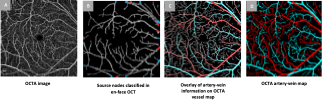

Our lab’s research interest is heavily focused on developing AI models for medical applications (Ophthalmology and Radiology), developing quantitative imaging biomarkers, and developing AI solutions for optical device instrumentation (optical coherence tomography angiography (OCT/OCTA)). Our current focus is on self-supervised and cross-modal machine learning and AI applications in medicine and healthcare, weak and semi supervised ML frameworks, and medical federated learning applications.